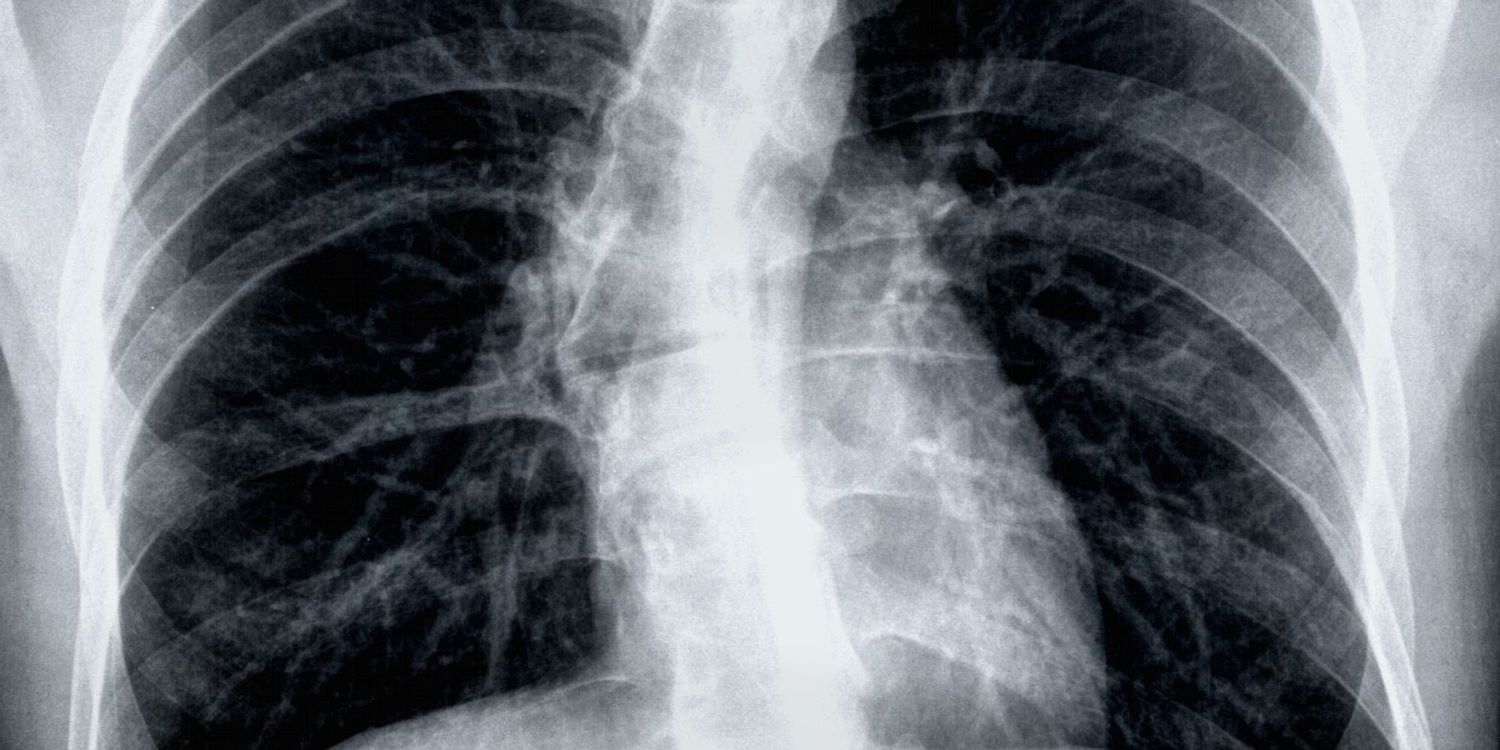

The Lung Cancer Screening Programme is designed to find out how well someone’s lungs are working and to identify any problems at an early stage. Most of the time no issues are found, but if cancer, lung or breathing issues are found early, treatment could be simpler and more successful.

- A scan of your lungs